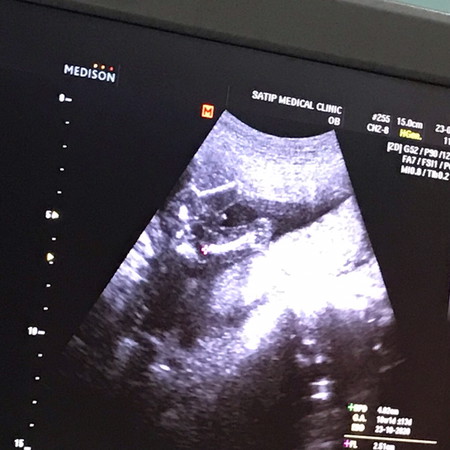

18w4วัน

จู๋โผล่แล้วครับ หนุ่มน้อยของแม่